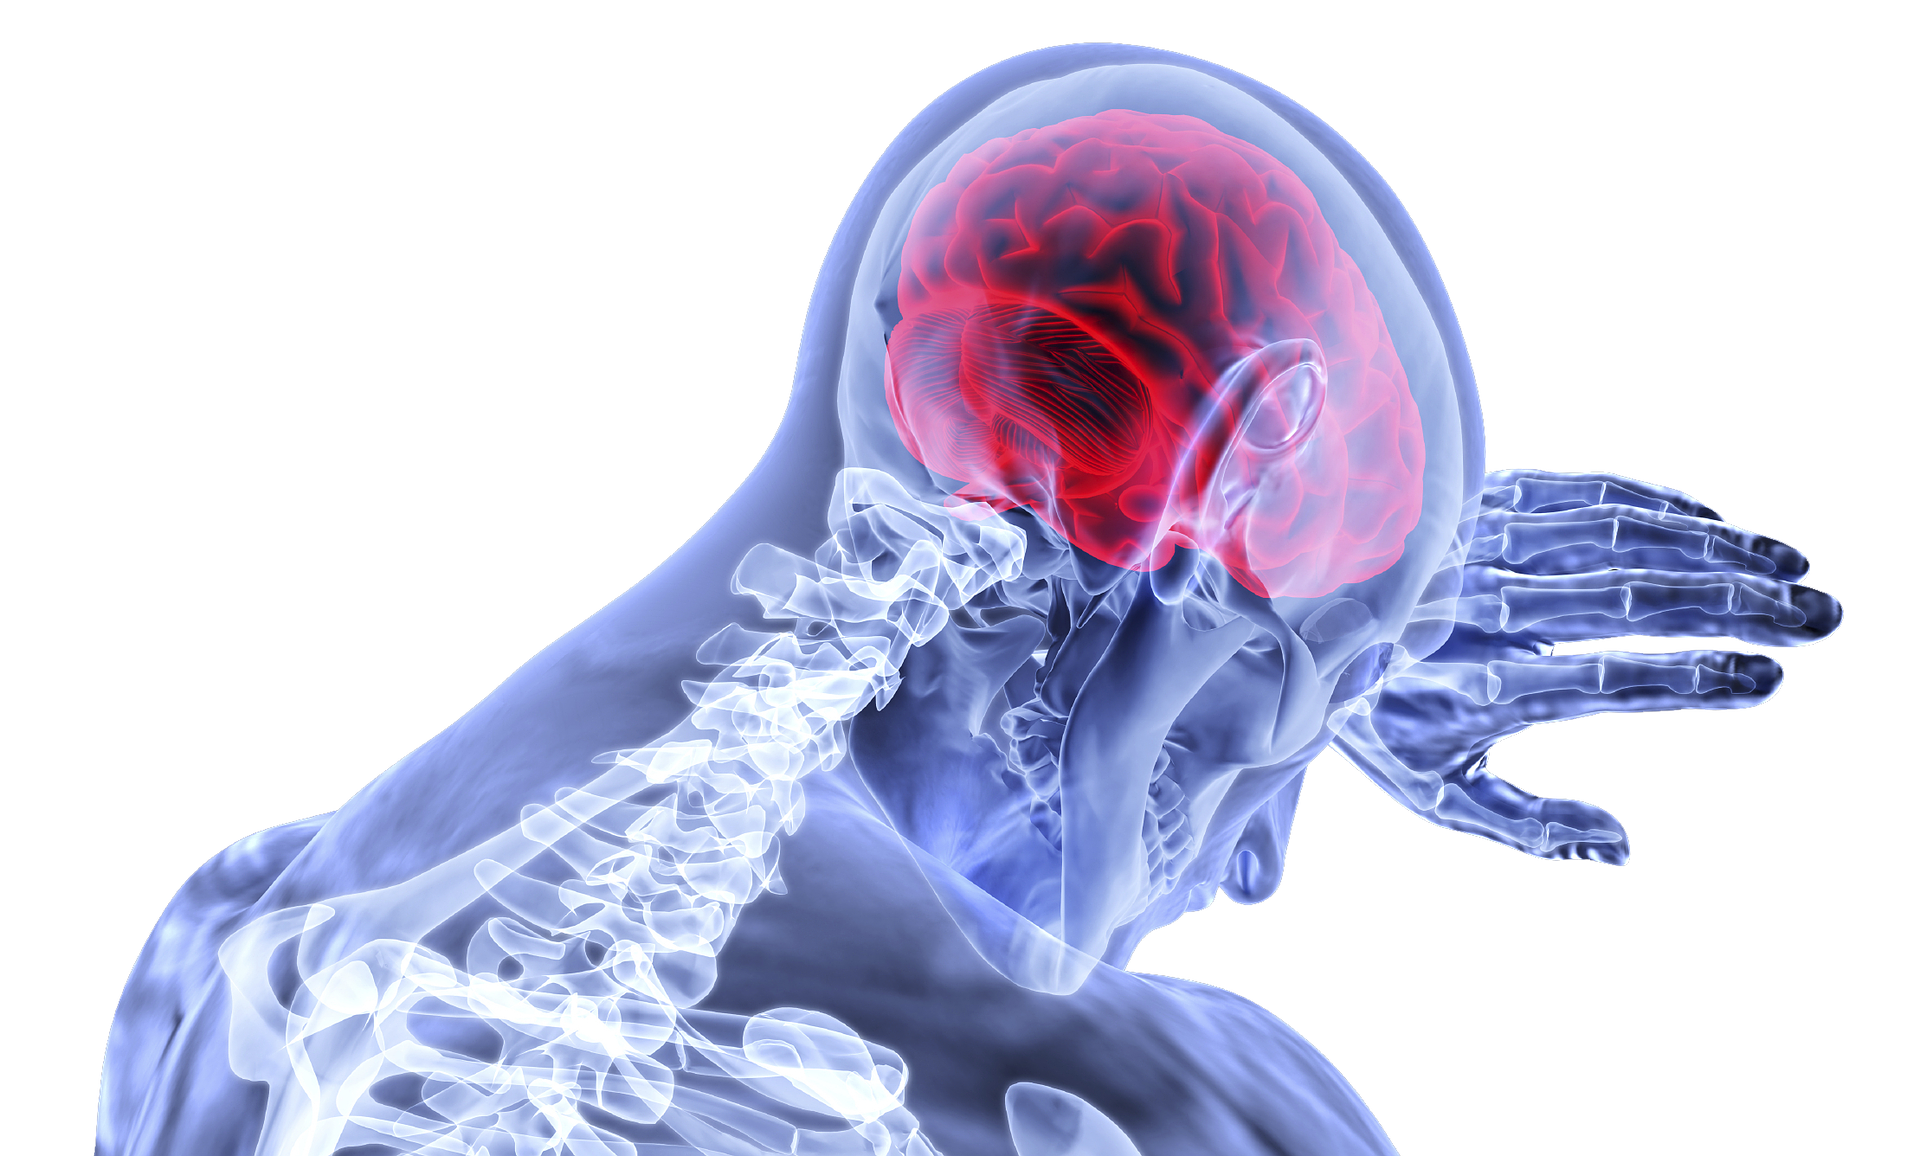

뇌혈관이 막히거나 터지는 질환을 부르는게 뇌졸중이고 그 중 뇌혈관이 막히는게 뇌경색 그리고 뇌혈관이 터지는 것을 뇌출혈이라고 합니다. 뇌졸중은 영구적인 손상이 많다고 하며 증상에 따라 전신이나 육체 일부 기능이 마비되는 등의 극심한 후유증이 남는 무서운 질병입니다 오늘은 뇌경색 초기증상에 대하여 알려드리도록 하겠습니다.

뇌경색 초기증상 3. 두통

뇌경색 초기증상으로 두통이 빈번하게 발생될 수 있는데, 목을 기준으로 목덜미 부위부터 통증이 시작되는데, 머리가 깨질 거 같은 고통이 생길 수도 있다고 하며 구토까지 나타날 수 있어요.